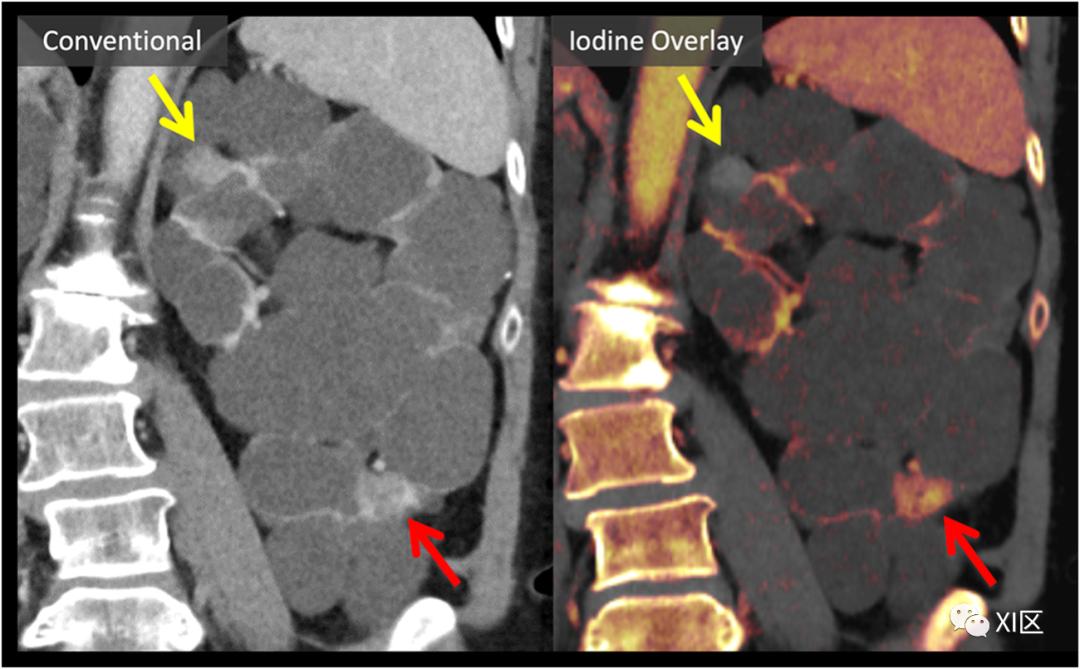

碘与其它高密度材料的鉴别

图5显示了血管内支架植入术后血管内漏和动脉瘤壁钙化情况下,在单次造影后扫描阶段碘和钙的区别。必须重申的是,在碘的两种和三种物质分解算法中,除算法中特定目标之外的物质在碘选择性图像和虚拟平扫图像中都呈现出不同程度的变化。因此,并不是碘图上显示的所有东西都真正代表碘,必须与匹配的VNC图像进行比较:虽然碘从VNC图像中完全减去,但钙的衰减大约在碘和VNC图像之间的一半被分割。因此,我们的常规自动DECT后处理包括在轴位和冠状位上匹配碘覆盖图和VNC图像序列。

肾损害评估与多囊肾

DECT碘选择性显像已被证明在根据病变内是否存在碘强化的基础上,有助于鉴别良性高密度囊肿和强化肾肿块。肾脏肿块评估通常包括多期肾脏肿块CT或MRI检查,包括平扫期、实质期和延迟期。由于扫描期相之间的错误配准限制了磁共振减影图像的应用,这些问题常常受到阻碍。然后,图像判读要求在手动放置的感兴趣区域中,在单独的、可能错误配准的扫描阶段对HU值(或MRI信号)进行比较。这对常染色体显性遗传性多囊肾病患者尤其具有挑战性,他们有更高的患肾细胞癌的风险,并且可能有比单纯液体衰减更高的多个病变。DECT可以简化多囊肾的评估,因为生成的碘含量本质上与VNC信息共同配准,如图7所示。这种方法已经被证明可以减少解释时间,并提高放射科医生对被评估的肾损伤中是否存在碘含量的信心。